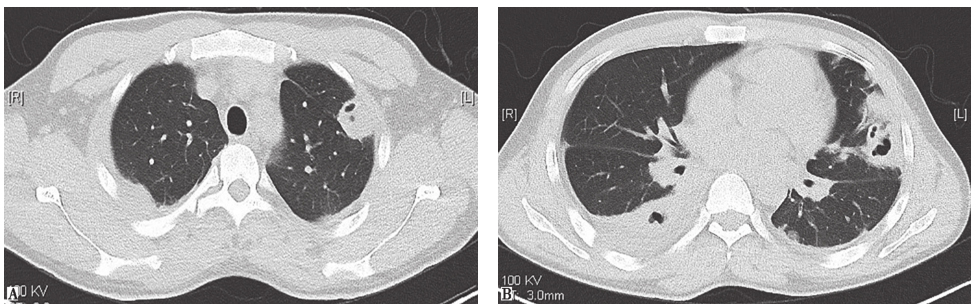

图4 肺隐球菌病胸部CT表现

CT可见右上肺多发结节影

图5 韦格纳肉芽肿病胸部CT表现

CT可见双肺多发多形结节影

图6 原发性肺淀粉样变胸部CT表现

CT可见双肺多发密度较为一致的结节影